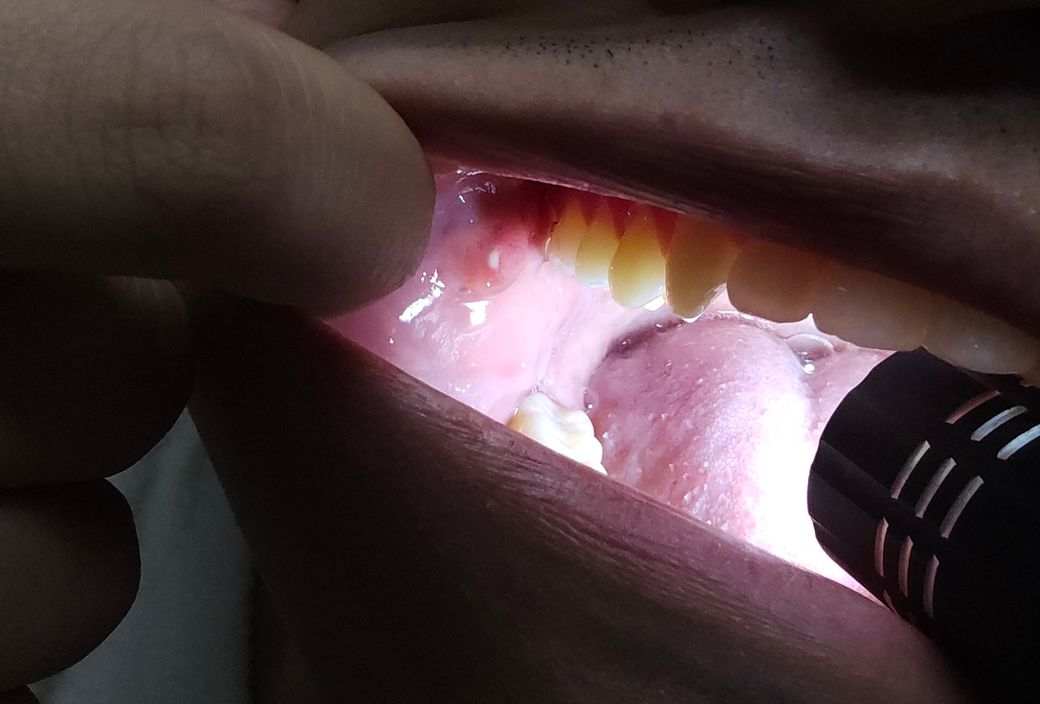

입안에 뭔가 화산처럼 솟아있고 중간엔 움푹 파여서 고름인지 뭔지 있는데 이거 뭘까요? 반대쪽에도 비슷하게 생긴 구멍이 있던데 이 기관에 염증이 생긴거 같은데 검색해도 안나오고 이게 먼지 궁금해요

구강 점막이 음식물을 씹는 도중 또는 치아로 인한 손상 또는 구내염의 가능성이 생각됩니다.

시간이 지나며 서서히 호전될 것으로 생각되므로 회복을 지연 시킬 수 있는 음주, 흡연, 지나치게 뜨겁거나 자극적인 음식 섭취를 피할 것을 권하며 만일 증상이 지속된다면 이비인후과 진료를 받기 바랍니다.